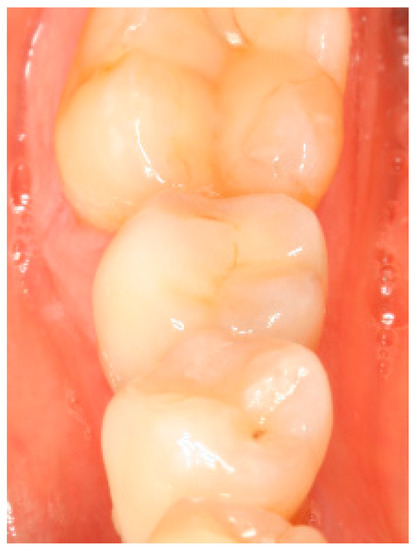

Clinical situation at the 3-year follow-up. Occlusal view.

Figure A7.

Figure A8.

Clinical situation at the 3-year follow-up. Lateral view.